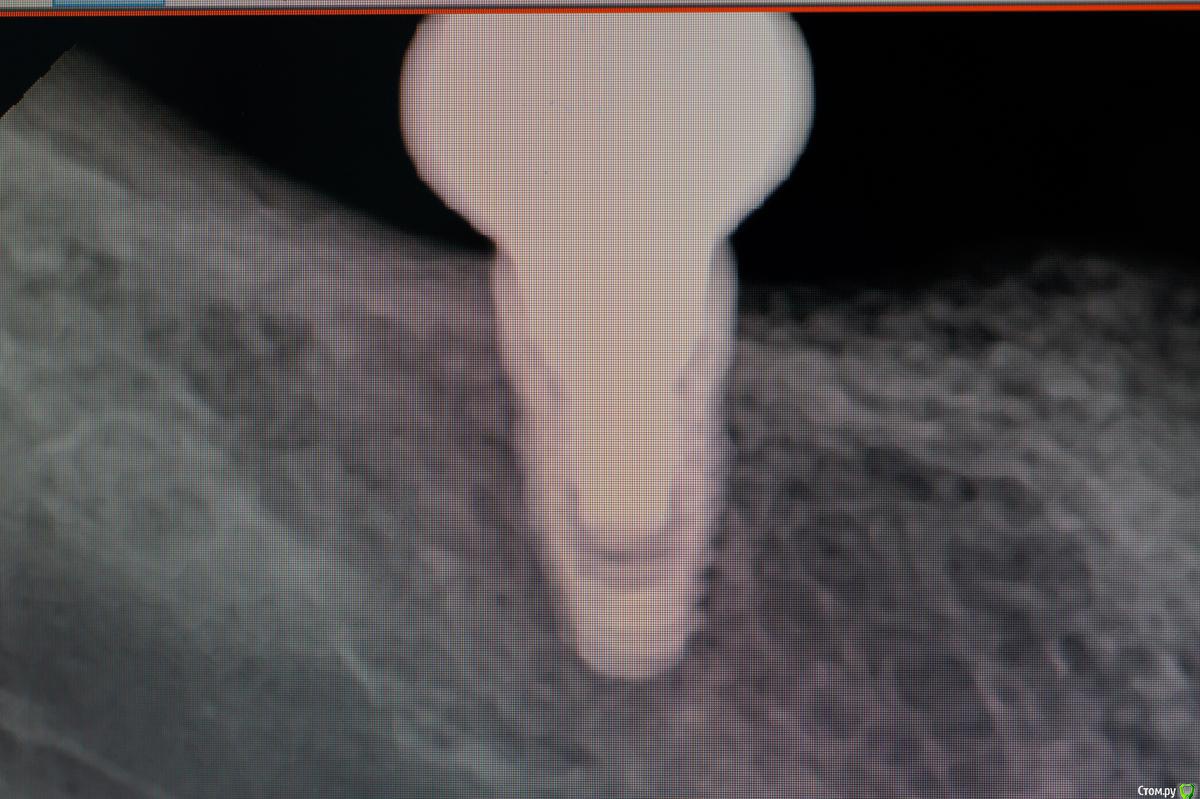

Des Опубликовано 22 мая, 2015 Поделиться Опубликовано 22 мая, 2015 Проблема с припасовкой каркаса при протезировании на имплантах (система Имплантиум): - каркас уходит язычноСлепочные трансферы для закрытой ложки установленыСлепок снят методом закрытой ложки А-силиконом i-Sil, шахты трансферов изолированы воском; аналоги имплантов подобраны правильно, но в слепок их устанавливал техник без моего контроля; на модели каркас установлен адекватно, аббатменты установлены в аналоги на модели правильно Вопрос: есть ли мнения на счет того, на каком этапе допущена ошибка?Мои предположения: либо искажения на этапе снятия слепка, либо техник неправильно поставил трансферы в слепок. Ссылка на комментарий

Aquarius Опубликовано 22 мая, 2015 Поделиться Опубликовано 22 мая, 2015 На фото модели - похоже с дистальным аналогом проблема Ссылка на комментарий

Des Опубликовано 22 мая, 2015 Автор Поделиться Опубликовано 22 мая, 2015 да нет, я просто его не закрутил абатмент до конца, когда фотографировал, в том то и дело, что на модели сидит нормально..... Ссылка на комментарий

Aquarius Опубликовано 22 мая, 2015 Поделиться Опубликовано 22 мая, 2015 да нет, я просто его не закрутил абатмент до конца, когда фотографировал, в том то и дело, что на модели сидит нормально.....Делаю ставку - либо абатменты - близнецы, которые техник не фрезеровал ни капли, грани их не совпадают рот-модель, либо не дозащелкнут дистальный аналог. Если все остальное точно в норме. А то был здесь случай, врач доказывал, что аналог выбран правильно, оказалось, что нет)) Ссылка на комментарий